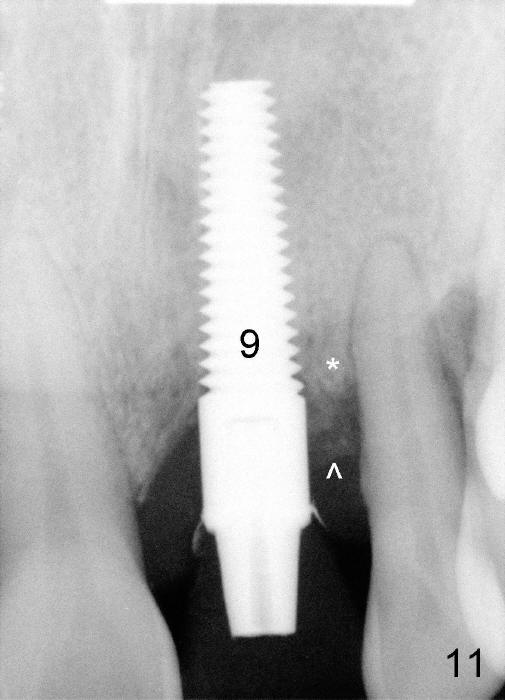

Six months postop, the patient returns because of loss of the provisional at the site of #7 (Fig.9). In fact, all of the three abutments are loose. They are permanently cemented. The provisionals are temporarily cemented (Fig.10,11). Surprisingly, the bone graft appears to survive (^). One of it appears to fuse with the crest (Fig.11 *, as compared to Fig.8).